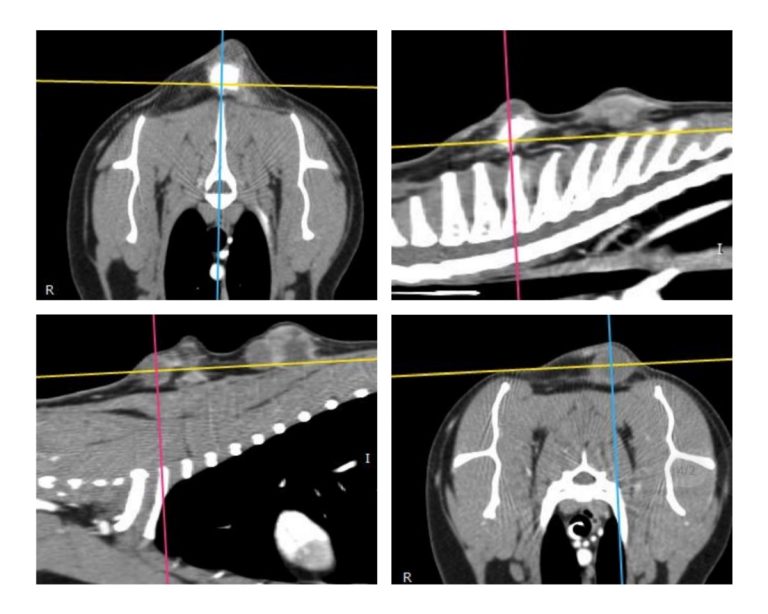

A daganat kiterjedésének meghatározása és a műtéti tervezés ideális esetben 3D képalkotó vizsgálattal (CT, MRI) történik, mely áttétkeresésre is alkalmas.

Injekció okozta szarkóma CT